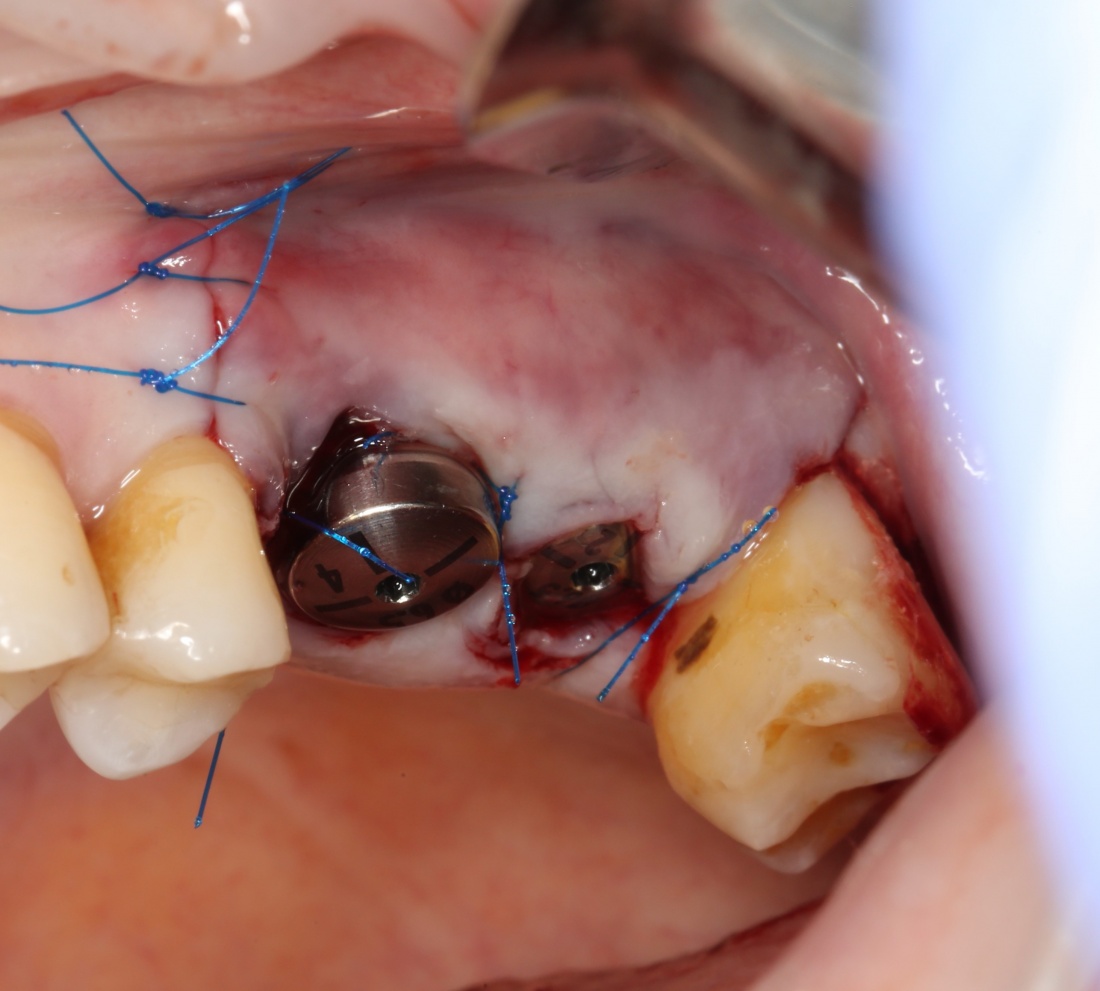

Глянем на то, что получилось:

Осталось адаптировать костный блок (убрать острые края), проверить его фиксацию и, при необходимости, добавить винты. Десятисекундное дело.

Если на этапе разреза и формирования раны всё сделано правильно, то наложение швов не вызывает особых трудностей. Периостотомия или послабляющие разрезы на периосте не требуются (ни практически никогда не требуются). А сами швы получаются аккуратными и герметичными:

Обрати внимание, что все шовные лигатуры находятся в пределах кератинизированной десны. Это позволяет избежать деформации тканей и лишних рубцов. В наиболее уязвимых местах (около зубов) шовные лигатуры лучше продублировать.